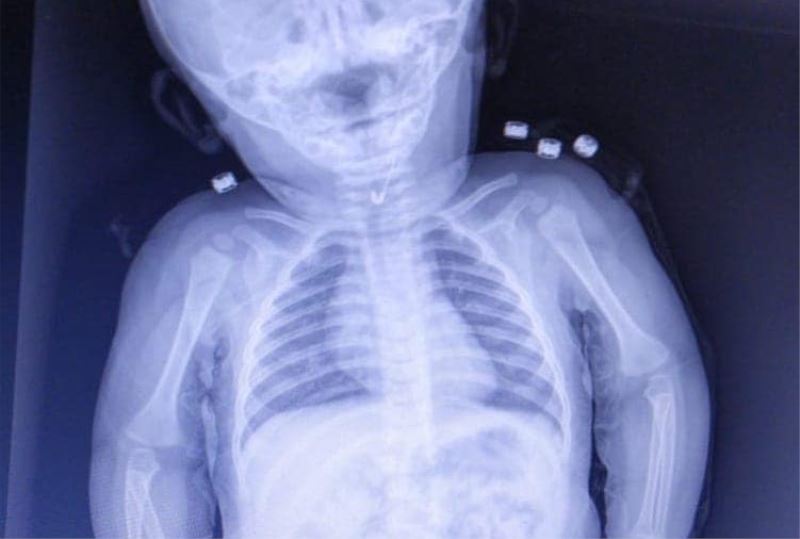

Tekirdağ’da 7 aylık bebeğin yemek borusundan ucu açık çengelli iğne çıktı.

Tekirdağ’da 7 aylık bir bebek, yemek borusuna çengelli iğine kaçması sonucu Tekirdağ Devlet Hastanesine sevk edildi. 7 aylık erkek bebeğin yutup yemek borusuna takılan açık çengelli iğne Tekirdağ Devlet Hastanesi’nde yapılan girişim ile başarıyla alındı. Gastroenterolojik Cerrahi Uzmanı Dr. İhsan Gündüz ile Anestezi Uzmanı Dr. İbrahim Çetin’in yaptığı operasyon sonucu bebek sağlığına kavuştu.